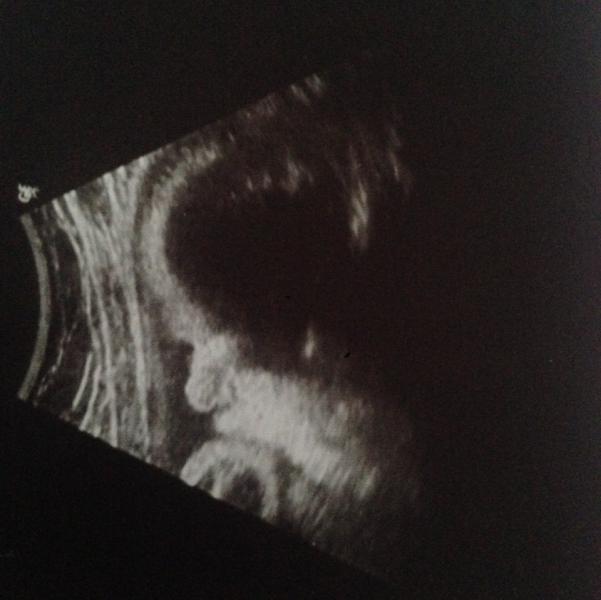

Ах да) забыла поделиться мы сегодня были на УЗИ) весим мы 2114)) лежим головкой вниз, и топчем маме печёнку😂😂 вот такая моя Маруся!